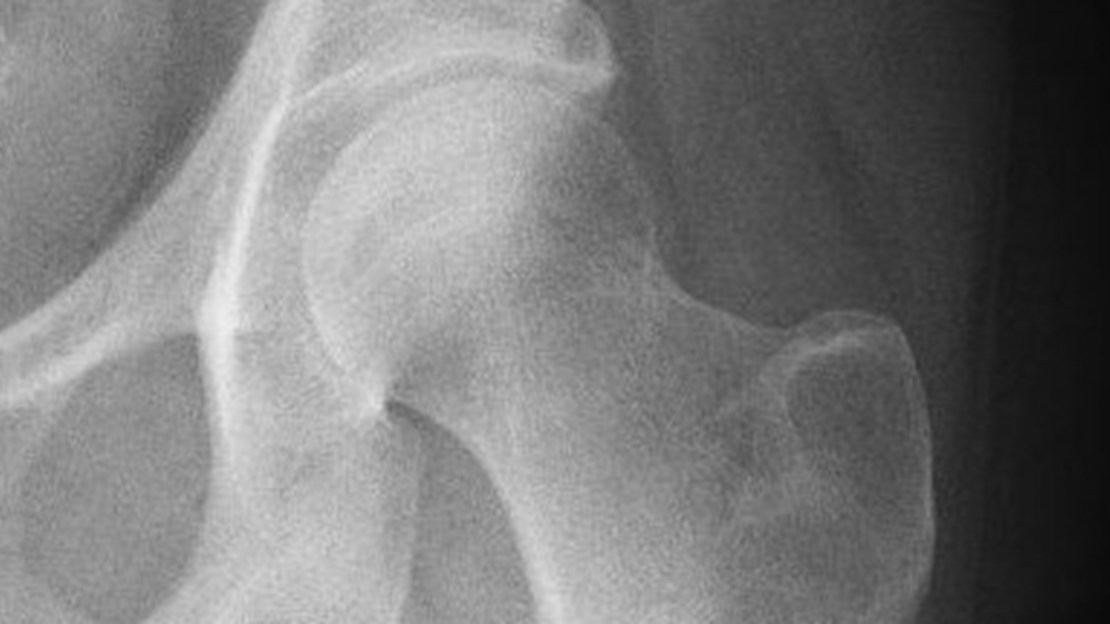

Il calcio e il magnesio rafforzano le ossa

Nel corpo umano il calcio e il magnesio sono da un lato componenti importanti delle reazioni metaboliche enzimatica e biochimiche, dall’altra sono responsabili della struttura del tessuto osseo e dentale, nonché della loro stabilità. Bevendo acqua potabile riusciamo però a coprire solo una parte del fabbisogno quotidiano. Il calcio e il magnesio vengono forniti principalmente dai latticini e dai prodotti a base di carne.